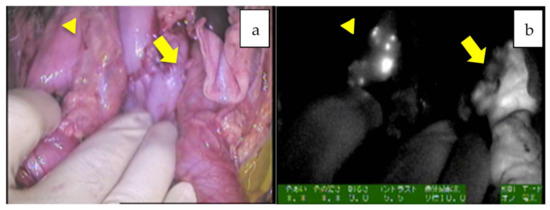

| 4 | 14 | 6m/M | PDE neo, D-light | right and left wedge resection | mixed epithelial and mesenchymal type, simple subtype | diffuse | left 1.5 mm, right 1 mm | 11623.9 | identification, newly detected tumors, false positive |

| 5 | 14 | 10 m/M | PDE neo system | right and left wedge resection | mixed epithelial and mesenchymal type, simple subtype | diffuse | 6.7 mm | 963.1 | identification, newly detected tumors, false positive, 34 m |

| 6 | 15 | 7y/M | PDE neo system | right wedge resection | mixed fetal + embryonal | diffuse | 3.5 mm, 2.8 mm, 1 mm, 3 mm, 3 mm | 3428.3 | identification, newly detected tumors, false positive, 34 m |